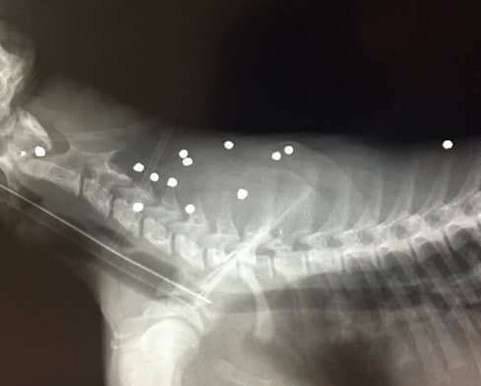

▼动物医院的兽医表示,这年纪的美洲豹本应属于活泼好动的,这头美洲豹却全身瘫软无力,但因为没有明显的外伤,所以决定用X光来诊断,结果发现牠体内竟有18颗子弹,不得不紧急进行手术。

▼在牠体内的18颗子弹中,其中两颗甚至伤及脊椎,情况令人担忧。